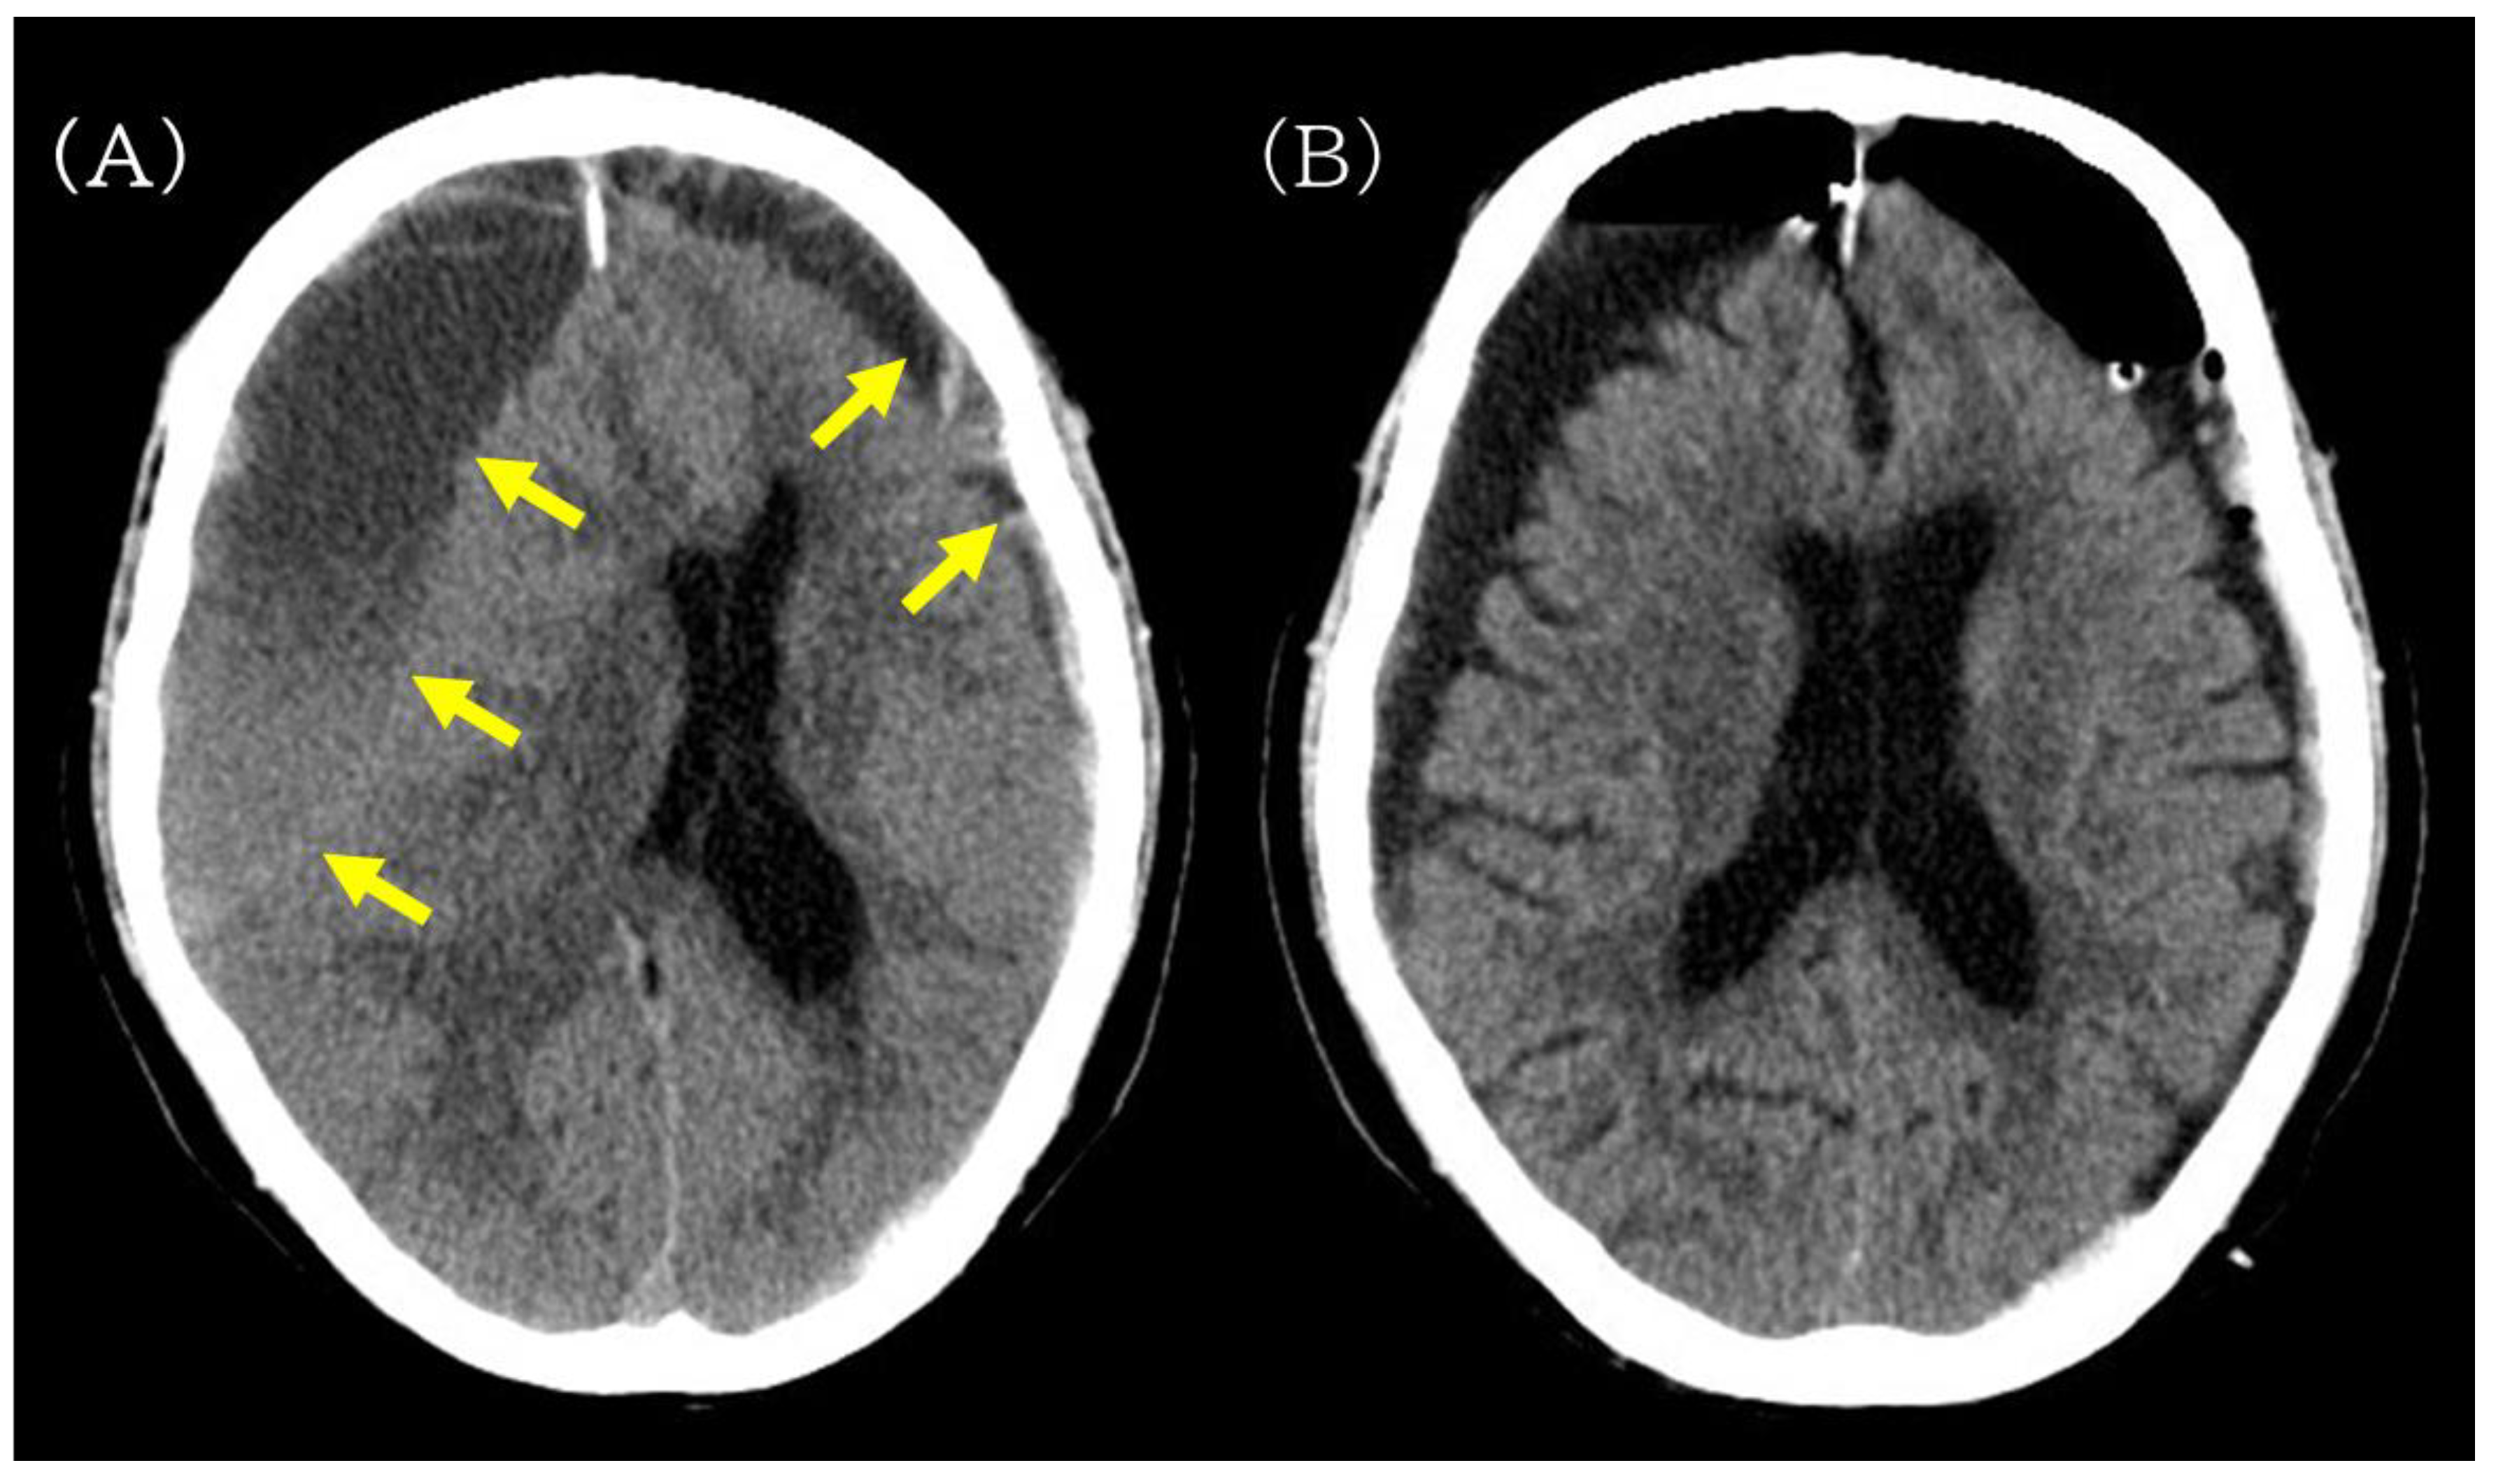

Figure 2.

Preoperative and postoperative non-contrast head CT images illustrating hematoma evacuation after burr-hole drainage. (A) Preoperative non-contrast head CT showing bilateral chronic subdural hematomas (yellow arrow), more prominent on the right, compressing both cerebral hemispheres. (B) Postoperative head CT obtained after burr-hole drainage showing reduced hematoma volume without new intracranial hemorrhage.

On the day of admission (postoperative day [POD] 0), right-sided burr-hole drainage of the CSDH was performed. The procedure was uneventful, and postoperative head CT confirmed adequate hematoma evacuation without new hemorrhage or acute brain swelling (Figure 2B). Cefazolin was continued perioperatively (2 g/day on POD 0 and 4 g/day on POD 1–3).